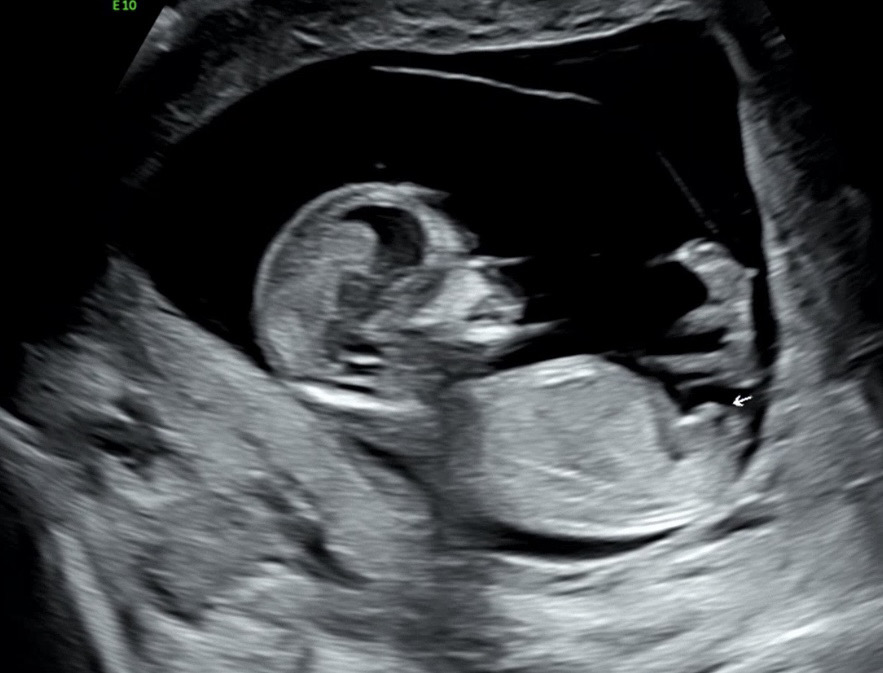

12주차 3일 애매한 각도법 도와주세요

애매하다고들 하셔서 ㅠㅠ 각도법 도와주세요!